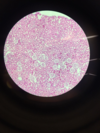

Kidney, silver impregantion